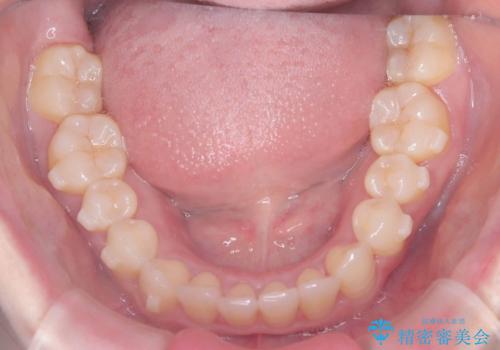

- 歯のデコボコと右上2番の歯の形が気になることを主訴に来院された患者様です。

軽度の叢生(凸凹)であったため、インビザラインのライトパッケージを用いて歯並びを改善しました。その後、右上2番はオールセラミッククラウンにより形態を回復し、審美性を向上させました。